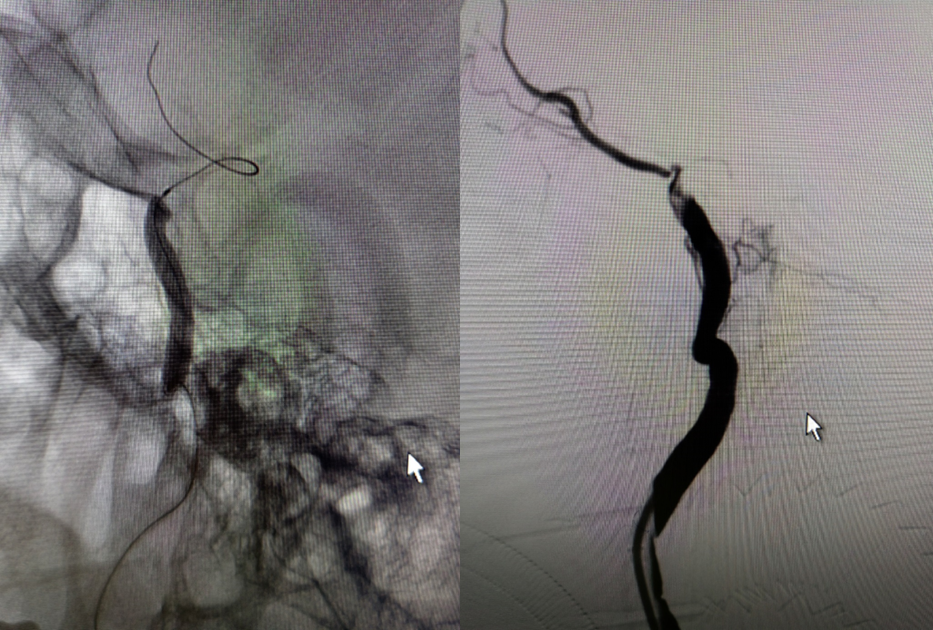

治疗中影像

Guiding到位,导丝通过病变。

球囊通过病变。

球囊扩张过程。

扩张后造影。

支架通过病变。

支架释放。

术后影像及检查

术后正位造影。

术后侧位造影